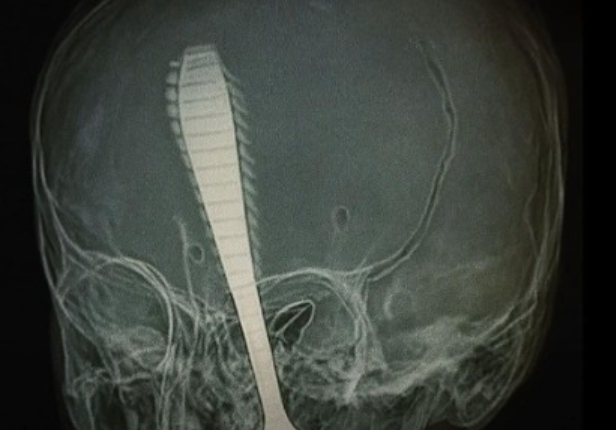

Uma menina de apenas 1 ano e 3 meses perdeu um dos olhos após sofrer um grave acidente doméstico envolvendo um objeto considerado comum no dia a dia: uma colher. O caso, que abalou a família e gerou forte comoção, reforça os riscos silenciosos presentes dentro de casa, especialmente para crianças pequenas que ainda estão em fase de desenvolvimento motor.

Segundo relatos dos familiares, a criança corria pelo ambiente segurando uma colherinha quando se desequilibrou e caiu. O impacto provocou um ferimento profundo na região do rosto, atingindo diretamente o olho. O socorro foi imediato, e a menina foi levada às pressas para atendimento médico especializado. Apesar da gravidade da lesão e da perda ocular, o quadro clínico geral da criança é considerado estável.

O reflexo natural das crianças ao cair, somado à falta de coordenação motora plena, aumenta a chance de que objetos atinjam regiões sensíveis do corpo, como olhos, boca e pescoço. Lesões oculares, em especial, podem causar danos irreversíveis em questão de segundos, como ocorreu neste caso.

Dados da área da saúde indicam que quedas são a principal causa de atendimentos de emergência envolvendo crianças pequenas. Quando associadas a objetos nas mãos, o potencial de gravidade aumenta consideravelmente, podendo resultar em perfurações, traumatismos faciais e danos neurológicos.